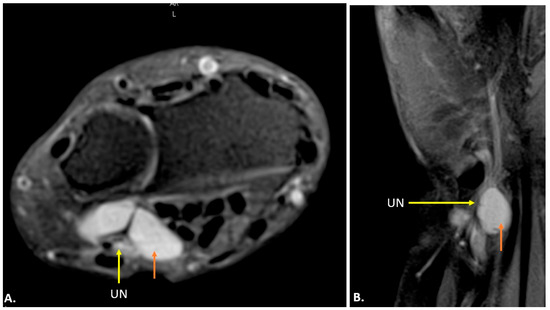

On MRI, ganglion cysts are well defined, hypointense on T1-weighted images, and hyperintense on T2-weighted images, reflecting their fluid content. Post-contrast images may show thin peripheral enhancement, but the cyst itself does not enhance. Unlike more complex cystic lesions, ganglion cysts usually do not contain calcific foci or haemorrhage. The cyst can cause displacement or compression of the ulnar nerve, which may show an increased signal on T2-weighted images, indicating oedema (Figure 7) [15].

Figure 7.

MRI reveals a well-defined, fluid-filled lesion within Guyon’s canal, consistent with a ganglion cyst (orange arrow), causing compression of the ulnar nerve (UN) (yellow arrow). Image (A) shows an axial view, while image (B) presents a long-axis view.